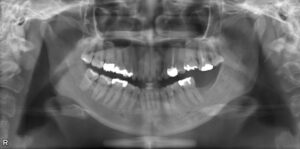

上下大臼歯2本欠損症例

BEFORE AFTER 37歳女性/上下2本欠損/インプラント埋込手術 【治療内容】 左下第二大臼歯は10年程前に抜歯…